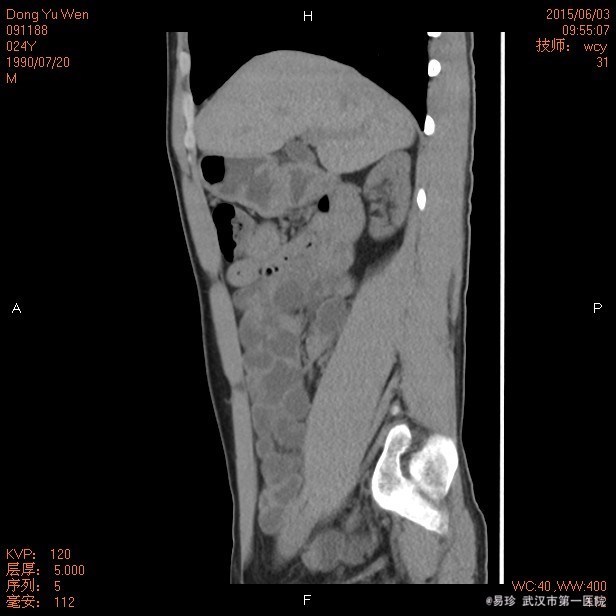

查体:生命体征平稳,听力下降,心肺听诊未见明显异常,腹软、无压痛,双下肢无水肿。 辅查: 泌尿系CT:双肾慢性肾病表现,双肾小结石,右肾轻度积液,右侧输尿管上段扩张,中下段显示不清。